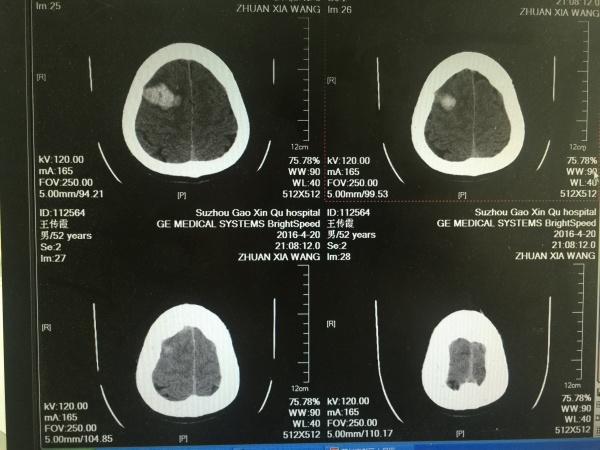

患者中年,女性,既往无高血压病史,此次因突发意识障碍1小时余入院,***血压230/123mmHg,神志呈昏睡,舌后坠,予以口咽通气道置入,急诊CT如下图,今日入院后第二日,复查颅内出血未见明显增加,因非高血压性脑出血常见部位,故行头颅CTA检查未见AVM及动脉瘤等血管病影像,病情现继观。